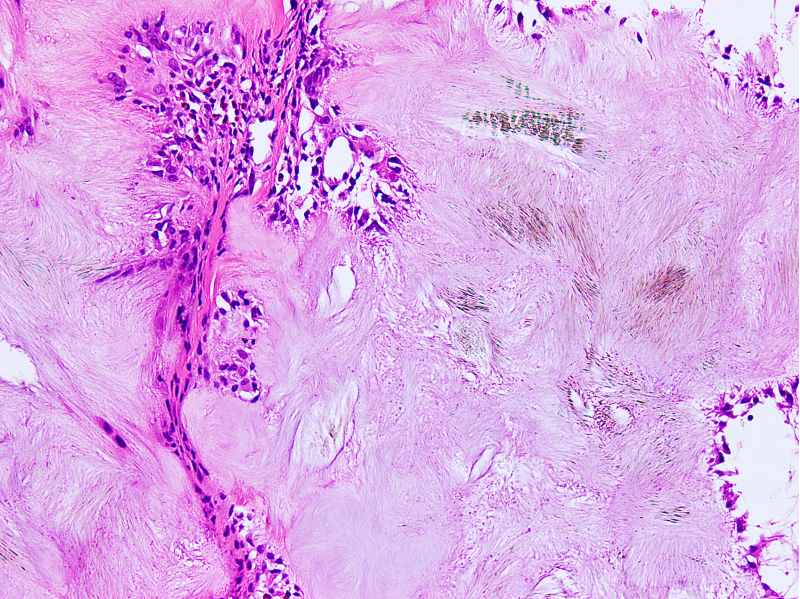

Microscopic (histologic) description

- Gout tophus:

- Nodular aggregates / granuloma-like appearance consisting of acellular, amorphous, pale eosinophilic material surrounded by palisading arrangement of histiocytes and multinucleated giant cells (Dermatol Online J 2015;21:13030)

- Feathery appearance in some deposits due to empty needle shaped spaces (Skeletal Radiol 2020;49:1325)

- Presence of monosodium urate crystals (MSU) is diagnostic

- Needle-like crystals that measure 5 - 25 micrometers in length

- Brightly anisotropic under polarized light

- Negative birefringence when examined with an interference plate in the light path (Otol Neurotol 2009;30:127)

- Crystals appear yellowish when aligned parallel to the plate axis

- Bluish appearance when alignment is across the direction of polarization

- Synovium changes:

- Affected synovium shows villous hyperplasia and synoviocyte hypertrophy and hyperplasia

- Typical chronic synovitis with mononuclear leukocyte infiltrate

- Urate crystals are also identified (Medicine (Baltimore) 1978;57:239)

Microscopic (histologic) images